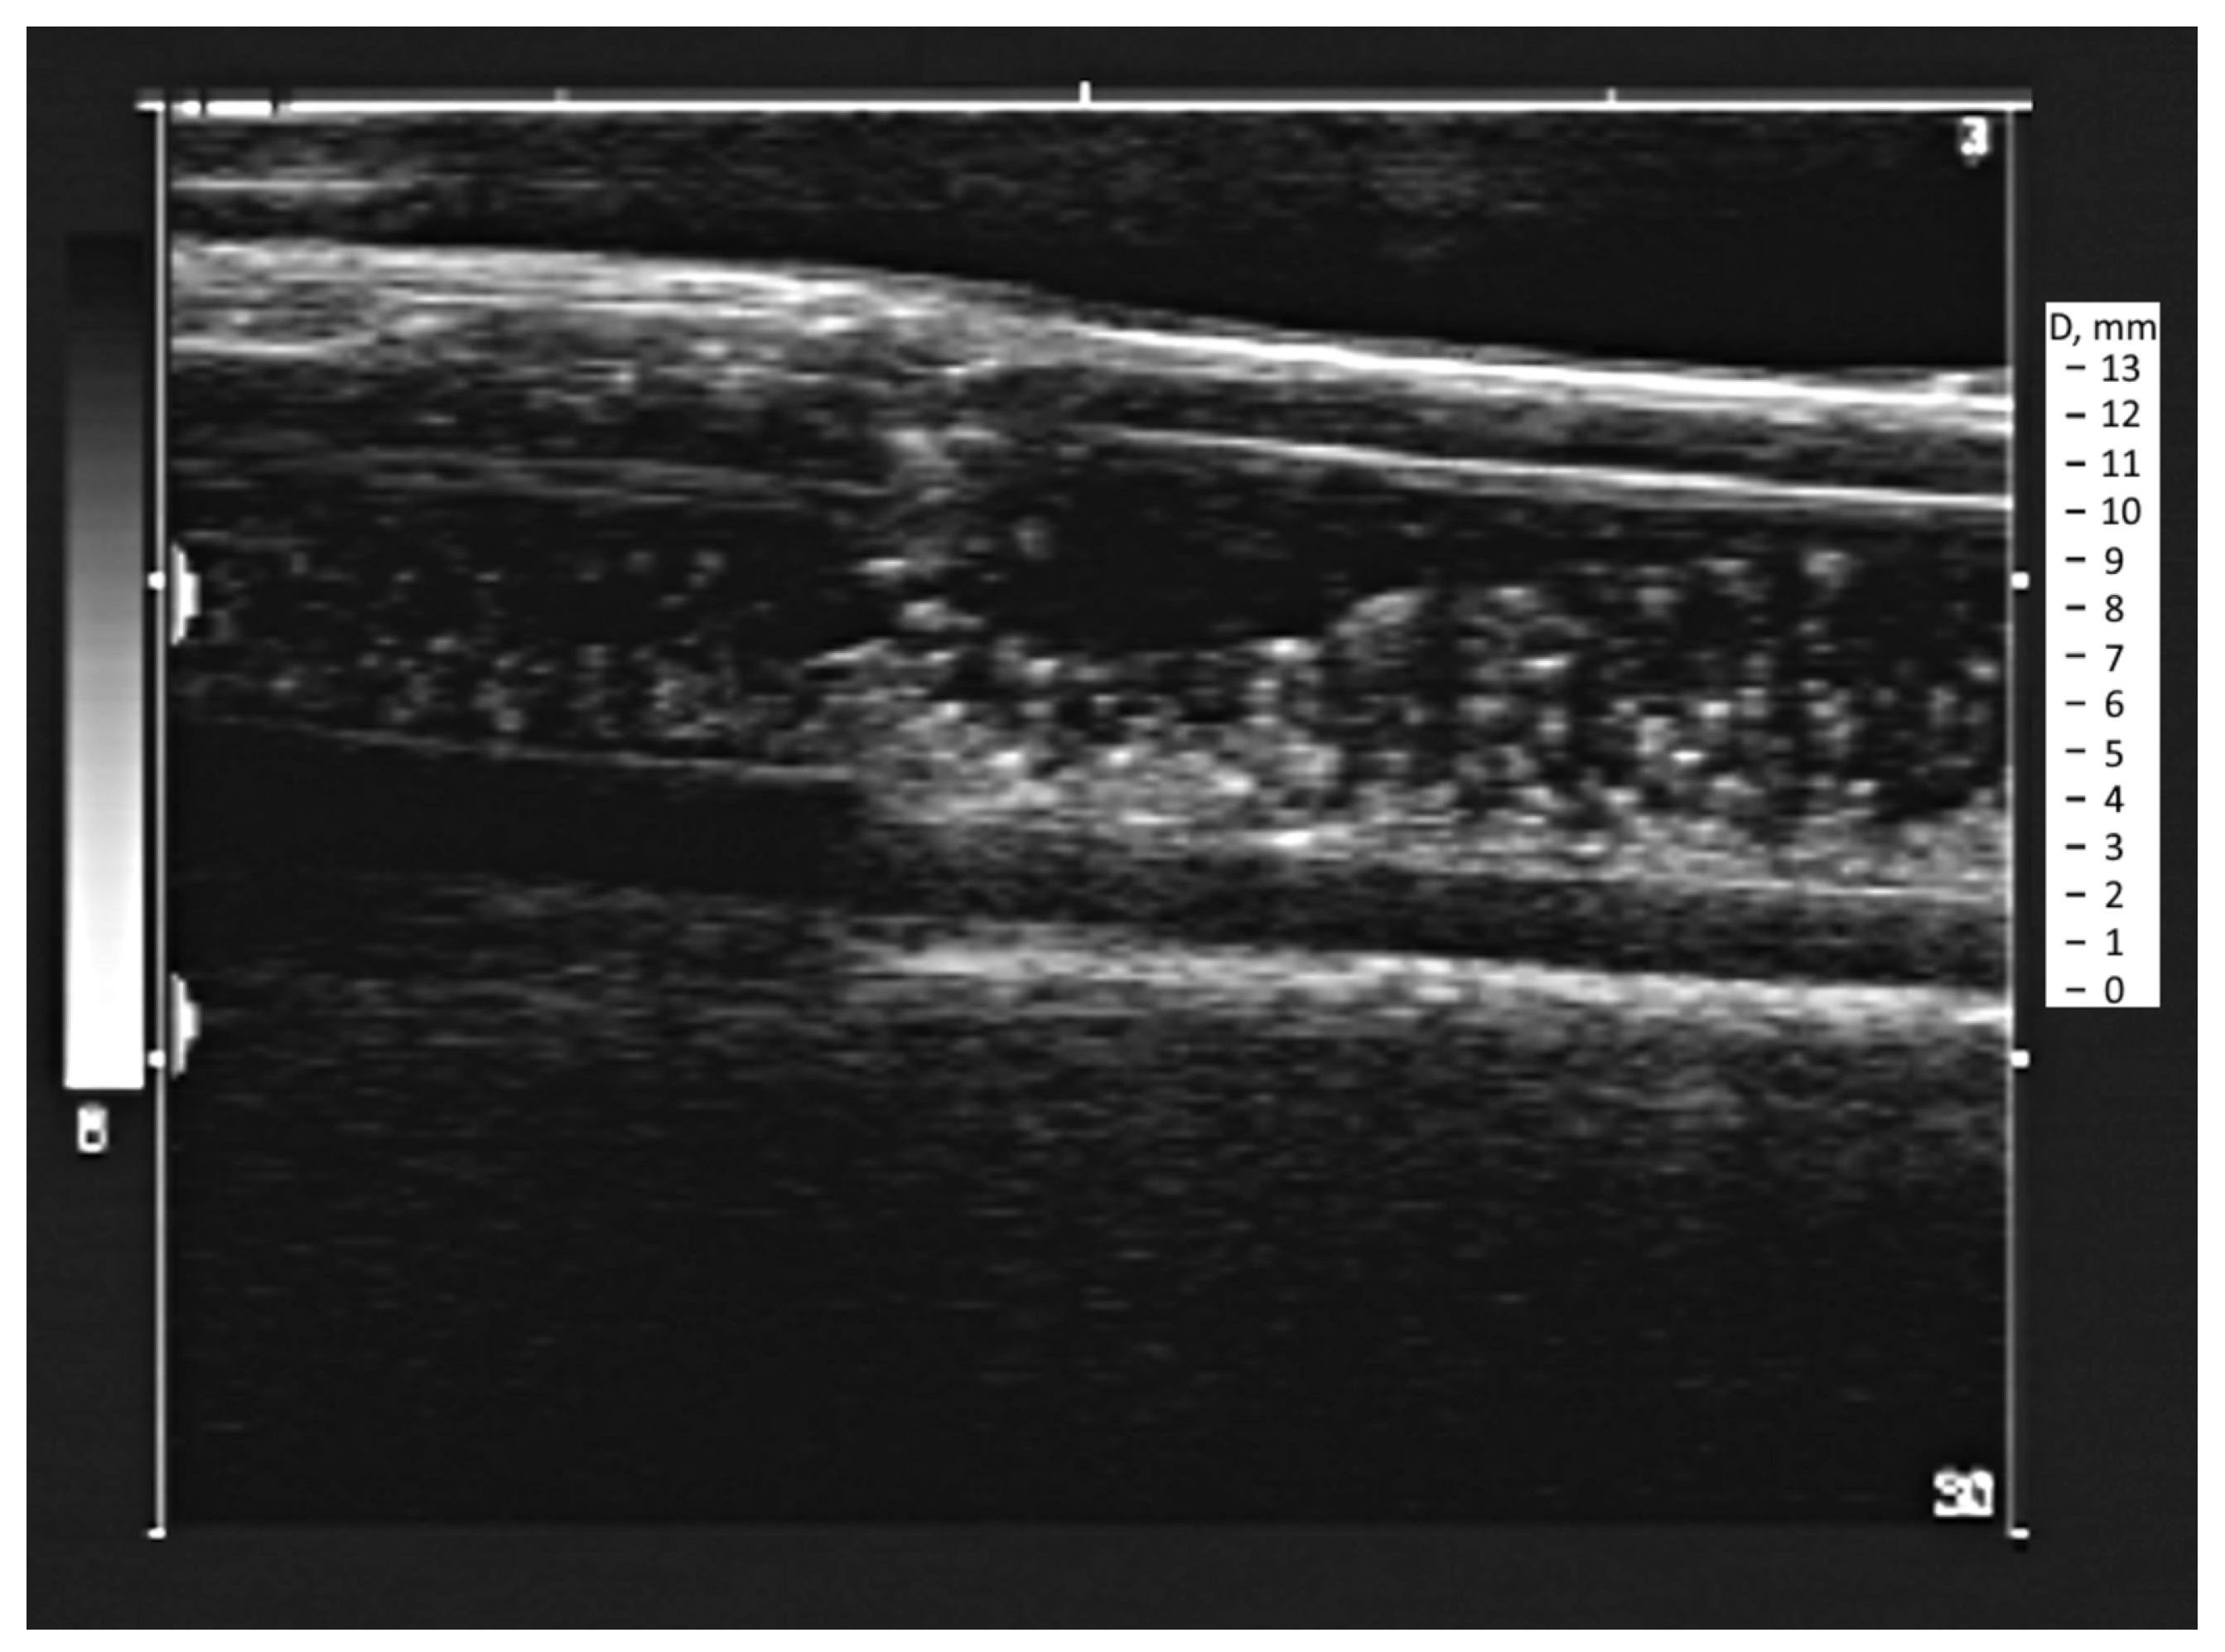

3.1. Obtaining the Vortex Zone by Echo-PV Tracking of Calcite Particles